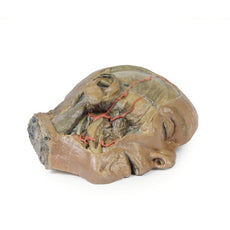

The head and neck of the specimen provides views of both superficial and deep structures in the region. The calotte has been removed ~2cm superior to the orbits to expose the brain in relation to the endocranial cavity. The transverse section through the cerebrum demonstrates the relation of the grey matter cortex to the white matter medulla, as well as the lateral ventricles with a small amount of choroid plexus visible in the base of both spaces. The skin and superficial fascia on the right side has been retained and false-coloured to display the angiosomes of the face and posterior neck. On the left side, the superficial tissues have been dissected to expose the muscles of facial expression, muscles of mastication, and deeper structures of the infratemporal fossa including the lingual nerve, terminal branches of the external carotid artery into the superficial temporal and maxillary arteries.

The carotid sheath has been opened on both sides of the neck, and the internal jugular veins and sternocleidomastoid muscles largely removed, to expose the pathway of the common carotid arteries, internal and external carotid arteries, and the vagus nerves. On the right side, the great auricular nerve ascends towards the face, while the hypoglossal nerve can be seen adjacent to the exposed stylohyoid ligament and supra- and infrahyoid muscles. A large thyroid gland is present bilaterally inferior to the thyroid cartilage, with a well-preserved superior thyroid artery and inferior thyroid vein on the right side and across the midline.

The head and neck of the specimen provides views of both superficial and deep structures in the region. The calotte has been removed ~2cm superior to the orbits to expose the brain in relation to the endocranial cavity. The transverse section through the cerebrum demonstrates the relation of the grey matter cortex to the white matter medulla, as well as the lateral ventricles with a small amount of choroid plexus visible in the base of both spaces. The skin and superficial fascia on the right side has been retained and false-coloured to display the angiosomes of the face and posterior neck. On the left side, the superficial tissues have been dissected to expose the muscles of facial expression, muscles of mastication, and deeper structures of the infratemporal fossa including the lingual nerve, terminal branches of the external carotid artery into the superficial temporal and maxillary arteries.

The carotid sheath has been opened on both sides of the neck, and the internal jugular veins and sternocleidomastoid muscles largely removed, to expose the pathway of the common carotid arteries, internal and external carotid arteries, and the vagus nerves. On the right side, the great auricular nerve ascends towards the face, while the hypoglossal nerve can be seen adjacent to the exposed stylohyoid ligament and supra- and infrahyoid muscles. A large thyroid gland is present bilaterally inferior to the thyroid cartilage, with a well-preserved superior thyroid artery and inferior thyroid vein on the right side and across the midline.